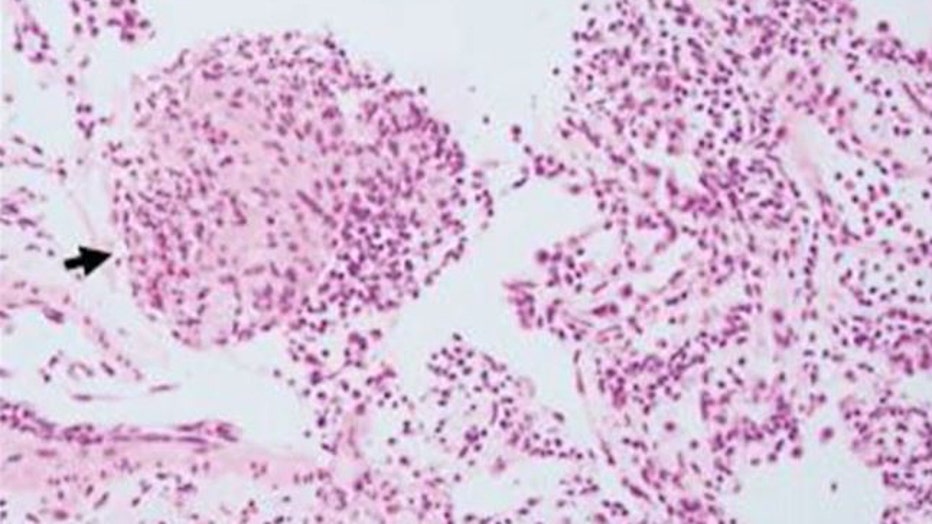

The creature was the larva of an Australian native roundworm not previously known to be a human parasite, named Ophidascaris robertsi. The worms are commonly found in carpet pythons.

Surgeon Hari Priya Bandi was performing a biopsy through a hole in the 64-year-old patient’s skull at Canberra Hospital last year when she used forceps to pull out the parasite, which measured 8 centimeters, or 3 inches.